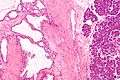

| Micrograph showing a pancreatic serous cystadenoma. H&E stain. | |

Pancreatic serous cystadenoma, also known as serous cystadenoma of the pancreas and serous microcystic adenoma, a benign tumour of pancreas. It is usually found in the head of the pancreas,[1] and may be associated with von Hippel-Lindau syndrome.[2]

In contrast to some of the other cyst-forming tumors of the pancreas (such as the intraductal papillary mucinous neoplasm and the mucinous cystic neoplasm), serous cystic neoplasms are almost always entirely benign. There are some exceptions; rare case reports have described isolated malignant serous cystadenocarcinomas.[3] In addition, serous cystic neoplasms slowly grow, and if they grow large enough they can press on adjacent organs and cause symptoms.

Pathologists classify serous cystic neoplasms into two broad groups. Those that are benign, that have not spread to other organs, are designated "serous cystadenoma".[4] Serous cystadenomas can be further sub-typed into microcystic, oligocystic (or macrocystic), solid, mixed serous-endocrine neoplasm, and VHL-associated serous cystic neoplasm. This latter classification scheme is useful because it highlights the range of appearances and the clinical associations of these neoplasms. Serous cystic neoplasms that have spread ("metastasized") to another organ are considered malignant and are designated "serous cystadenocarcinoma".

Pathology